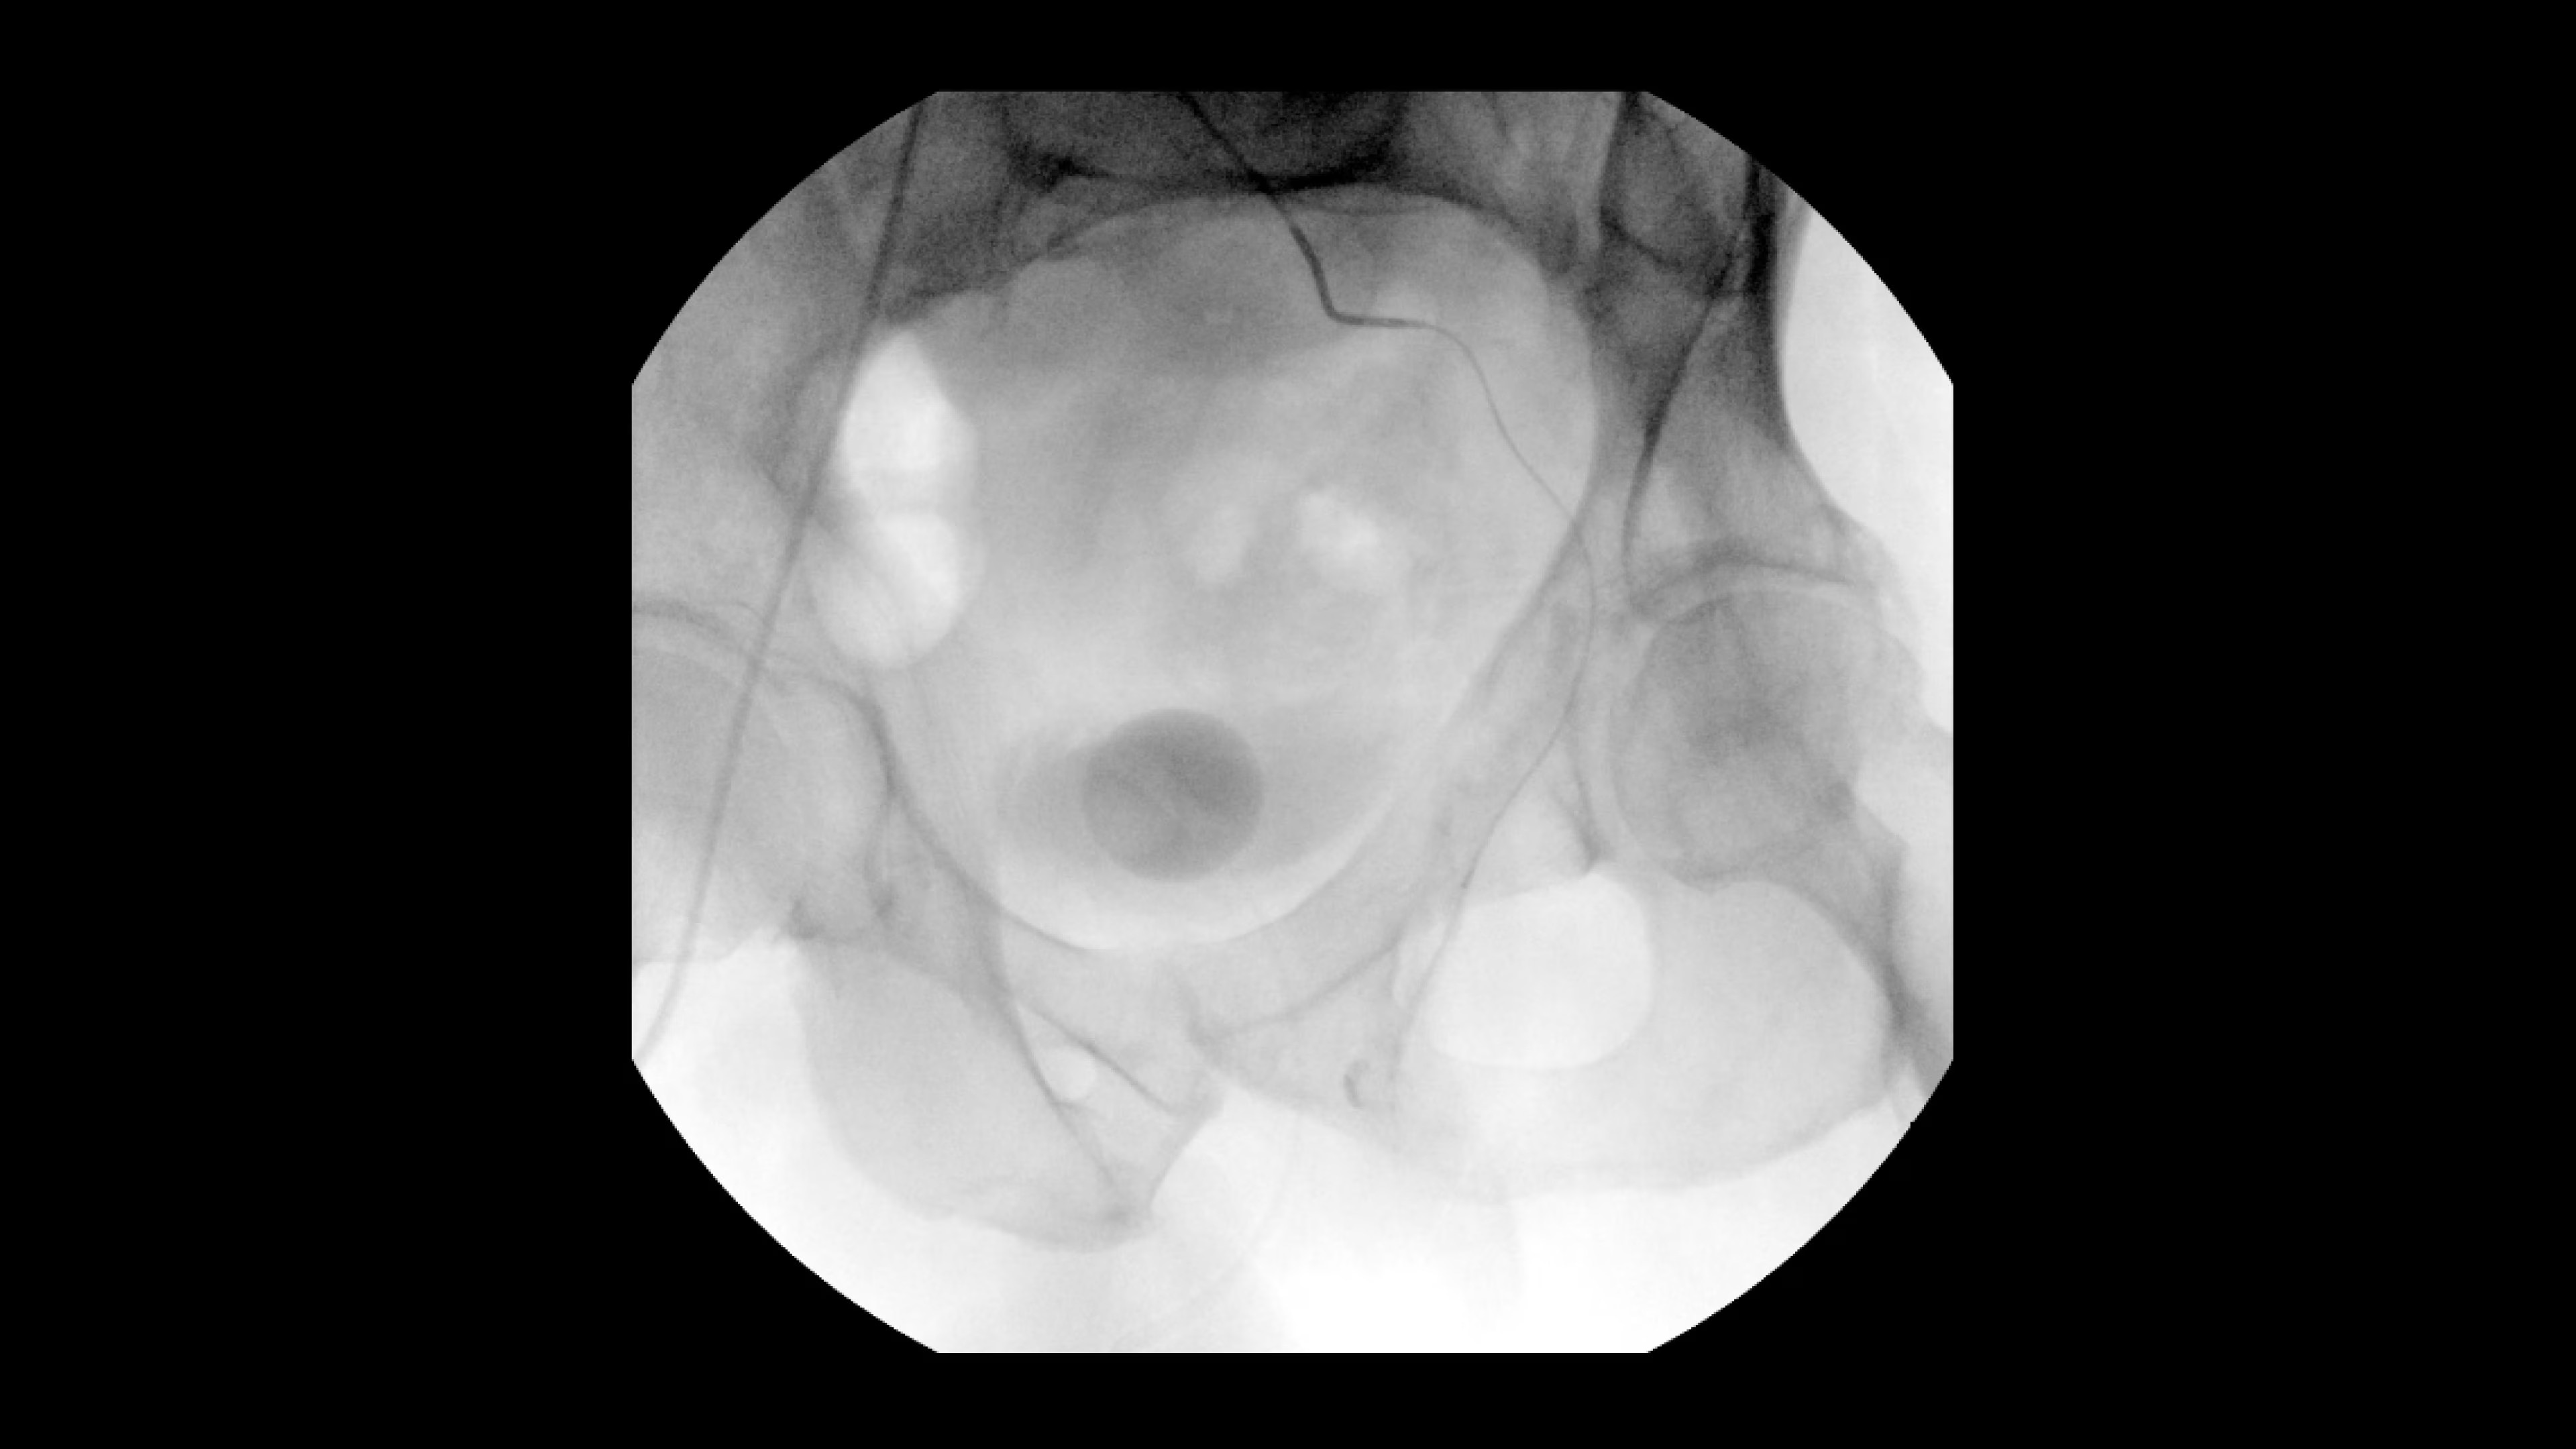

Achieve clear and detailed visualization during a variety of interventional procedures. OEC C-arms also bring efficiency to operating suites through a variety of C-arm options, including mobile cone beam CT.

See 0.014” guidewires in chest and abdomen region or 0.008” guidewires in peripheral vascular on a large 4K display.

Experience fixed room-like images with eNR (enhanced Noise Reduction), an advanced software algorithm that automatically reduces image noise by 30%* for an equivalent appearance of

30 kW power.

Digitally zoom up to 4X during a fluoro shot or Cine with no change in dose by using Live Zoom.